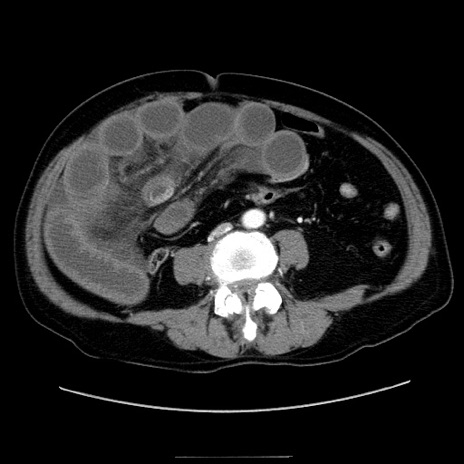

症例30(横断像)

【症例】80歳代男性

【主訴】臍周囲痛

【現病歴】約6時間前から臍下部痛が出現。次第に腹部膨隆・背部痛も生じてきたため来院。背部痛の場所は変化しない。

【既往歴】腎盂腎炎

【身体所見】意識清明、BT 36.3℃、BP  131/87mmHg、P 87bpm、SpO2 100%(RA)、臍周囲自発痛・圧痛あり、反跳痛なし、自発痛部位に一致して板状硬あり、腹部膨隆、腸雑音減弱、CVA tenderness両側陰性。

【データ】WBC 19600、CRP 0.33